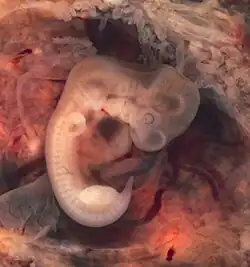

Die körperliche Entwicklung während der Pränatalzeit – insbesondere die des Gehirns – ist von besonderer Bedeutung für die Pränatalpsychologie. In den ersten acht Wochen nach der Befruchtung der Eizelle wird das heranreifende Kind als Embryo bezeichnet. Nachdem die inneren Organe ausgebildet sind (ab der neunten Entwicklungswoche) wird die Bezeichnung Fötus (oder Fetus) verwendet.

Der Physiologe Davenport Hooker untersuchte in den 30er Jahren des zwanzigsten Jahrhunderts Reflexe bzw. Reaktionen von abgetriebenen Föten extrauterin.[4] Die motorischen Fertigkeiten von Embryo und Fötus lassen sich mittlerweile mit Hilfe der Ultraschalltechnik vergleichsweise gut empirisch untersuchen. Ab der 8. Woche bewegt der Embryo bereits den Rumpf, kurz danach zeigen sich Bewegungen der Extremitäten.[5] Mit Hilfe der Ultraschalltechnik ließ sich nachweisen, dass es sich hierbei nicht nur um Reflexe handelt, sondern auch um endogen ausgelöste Bewegungen.[6] Nach Auffassung von Alessandra Piontelli zeigt der Fötus alle Bewegungsmuster, die später dann auch beim neugeborenen Baby gefunden werden.

Atembewegungen sind ab der 10. Woche beobachtbar, dabei wird Fruchtwasser in die Lungen aufgenommen.[7] Ab der 18. Woche lassen sich Augenbewegungen nachweisen, ab der 23. Woche entstehen rapid-eye-movements (REM-Phasen).[8] Diese hängen wohl mit Schlafmustern und Träumen zusammen. Föten trinken Fruchtwasser und geben Urin in das Fruchtwasser ab.[9]